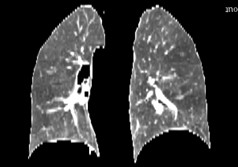

2.4 连通域

最后保留最大的连通域,此时最大的连通域就是肺部。